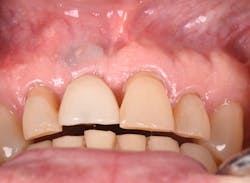

The Er:YAG laser has been more recently known for its ability to remove calculus from a titanium implant surface as well as detoxification (figures 17–21).9 Many authors have shown the laser’s use in combination with mechanical debridement to be superior when using a regenerative approach to treat peri-implant diseases (figures 22–26).10 A particular feature of this laser is the microexplosions that occur when the laser energy is absorbed by water. The volume of these explosions suddenly expand up to 1,000 times, covering more surface area of a titanium implant. It has been found that both contaminated debris and the contaminated oxide layer are removed as a result of these microexplosions.11

Figure 17: Patient presented with buccal vestibule swelling and complaining of pain. Swelling is visible and palpable with discoloration of the soft tissue.

Figure 18: Pre-op radiograph shows retrograde peri-implantitis possibly from previous periapical pathology.

Figure 19: Immediately after incisions and raising a full-thickness flap, suppuration was noted on the apex area of the implant.

Figure 20: An osteotomy was done to access apical area of implant No. 8 utilizing the Er:YAG laser at 20 pps/70 mJ. The then-exposed area was irradiated using a combination of detoxification and biostimulation of the bone and implant to prepare the area to receive a bone graft.

Figure 21: After mechanical debridement and surface detoxification

Figure 22: A regenerative approach was taken using a xenograft bone graft in combination with BB human recombinant platelet-derived growth factors.

Purchasing the Er:YAG laser can be beneficial to clinicians who desire a true hard- and soft-tissue laser. The amount of training is minimal, and the settings are similar for various applications. Since the Er:YAG laser has an affinity to water, it has been shown to have minimal thermal changes, and it promotes reduced postoperative discomfort. One study showed that when cutting bone for partially erupted third-molar extractions, not only less intra- and postoperative pain was noted, but also a reduction in facial swelling when compared to conventional bur drilling.13

Figure 23: A porcine 3-D volume stable collagen matrix was used not only as a barrier but also to enhance the thickness of the soft tissue. The matrix thickness measured 3 mm to achieve gingival horizontal volume.

Figure 24: Immediate post-op of gingival tissue repositioned tension-free.

Figures 25 and 26: One-year postsurgery. Clinically all signs of retrograde peri-implantitis have been eliminated and radiographic bone fill can be seen.